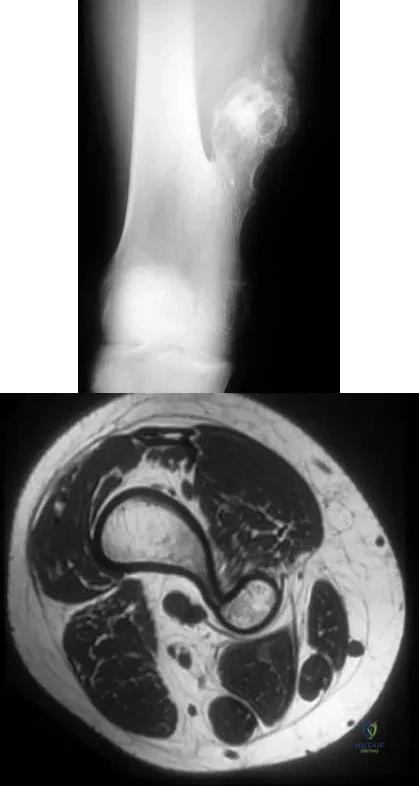

Examination of a 12-year-old girl with a painful flatfoot deformity reveals tenderness in the region of the sinus tarsi and no appreciable subtalar motion. Radiographs are shown in Figures 48a through 48c. Two attempts to relieve her symptoms by cast immobilization fail to relieve the pain. Management should now consist of

A 28-year-old woman who is training for the New York Marathon reports pain in the posteromedial aspect of her right ankle. Examination reveals tenderness just posterior to the medial malleolus. Radiographs are normal. An MRI scan is shown in Figure 3. What is the most likely diagnosis?

A 17-year-old boy has had a mass in his right thigh for the past 6 months. He denies any history of trauma. Examination reveals that the mass is painless and firm. A radiograph and axial MRI scan are shown in Figures 49a and 49b. What is the most likely diagnosis?